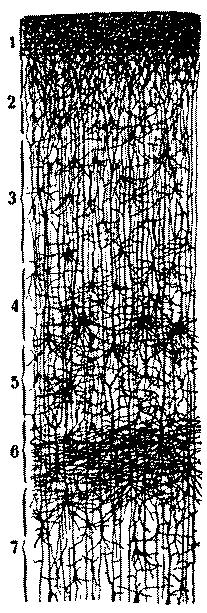

| 6. | Layers of the posterior central or ascending parietal convolution of a new-born child | 112 |

| 7. | Diagram of cells of cerebral cortex | 113 |

| 13. | Deep layer of giant pyramidal cells of the posterior central or ascending parietal convolution of a child thirty days old | 119 |